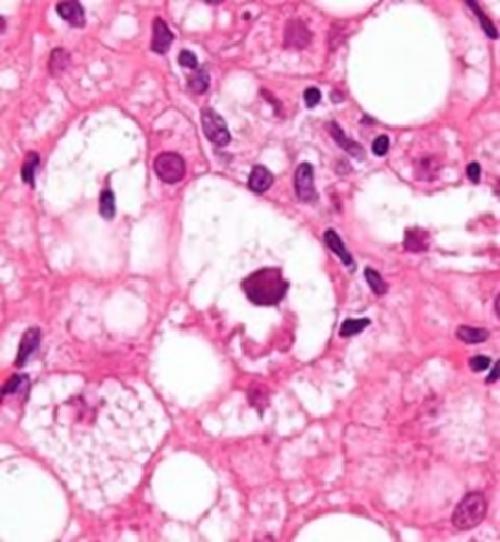

Клетки поражённого органа

Ожирение печени алкоголика или, по-научному, гепатоз, представляет собой патологию, в результате которой происходит трансформация нормальной и здоровой ткани печени в жировую, при этом, сильно поменяв структуру и состояние органа. Данное заболевание можно отнести к рефлексивной реакции организма на отрицательное действие ряда факторов, главным из которых считается токсическое свойство, вызванное распитием спиртосодержащей продукции. Поэтому частый прием спиртного ведет к быстрому обрастанию печени жиром, лечение которой будет трудным и долгим. Важно: помимо печени, при распитии алкоголя происходит поражение жиром и других органов, к примеру, поджелудочной железы.